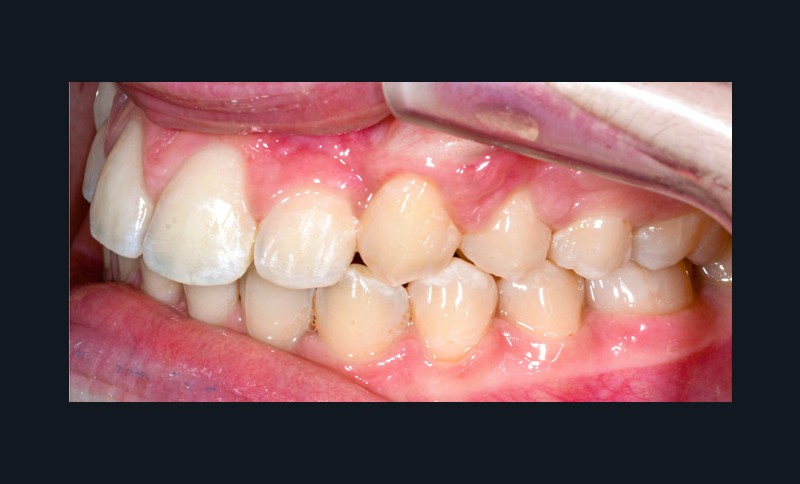

La patiente consulte à l’âge de 9 ans pour la malposition de ses incisives latérales maxillaires. Elle présente une occlusion de Classe I bilatérale sur un schéma normodivergent avec une dysharmonie dento-maxillaire en denture mixte. À l’arcade maxillaire, elle présente une endoalvéolie avec rotations mésiopalatines de 16 et 26.

Sur la radiographie panoramique, on observe une transposition des canines maxillaires en place d’incisives latérales, au contact des racines de 11 et 21.